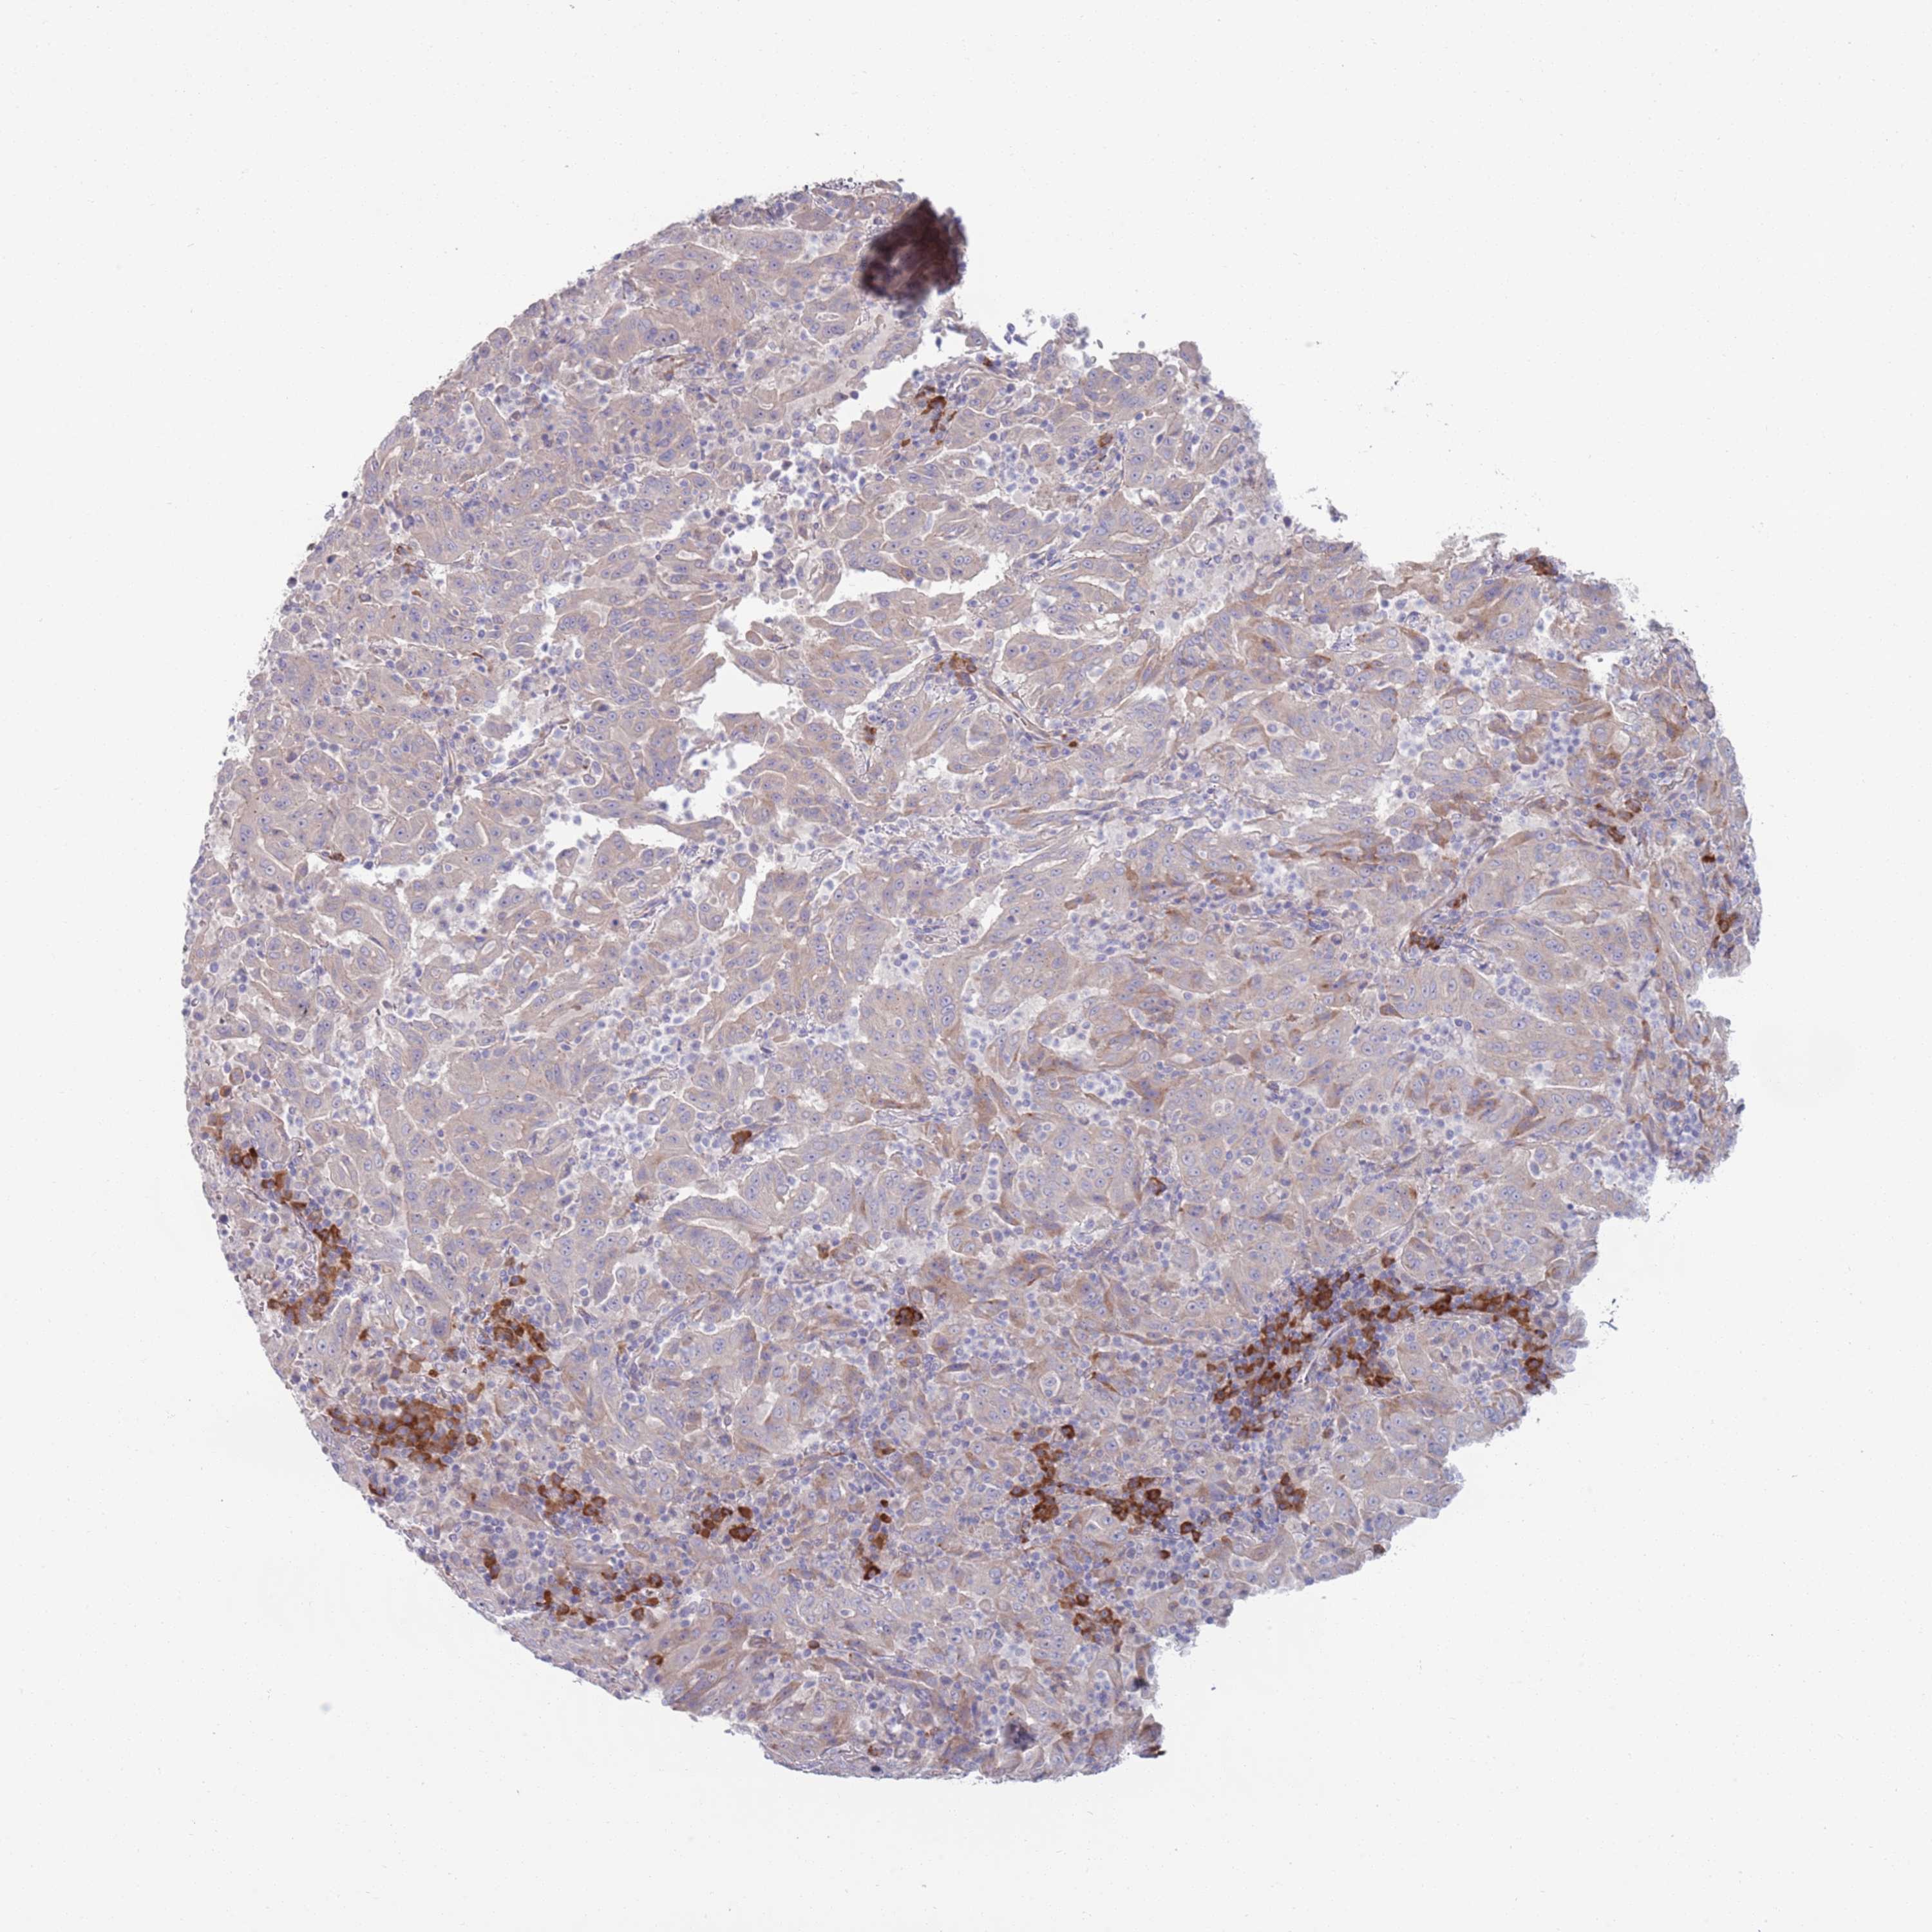

PANCREATIC CANCER - Protein expressioni

A mouse-over function shows sample information and annotation data. Click on an image to view it in a full screen mode. Samples can be filtered based on level of antibody staining by selecting one or several of the following categories: high, medium, low and not detected. The assay and annotation is described here.

Note that samples used for immunohistochemistry by the Human Protein Atlas do not correspond to samples in the TCGA dataset.

Antibody stainingi

Antibody staining in the annotated cell types in the current human tissue is reported as not detected, low, medium, or high, based on conventional immunohistochemistry profiling in selected tissues. This score is based on the combination of the staining intensity and fraction of stained cells.

Each image is clickable and will lead to virtual microscopy that enables deeper exploration of all samples and also displays staining intensity scores, fraction scores and subcellular localization as well as patient and tissue information for each sample.

Antibody HPA048884

Staining

High

Medium

Low

Not detected

Intensity

Strong

Moderate

Weak

Negative

Quantity

>75%

75%-25%

<25%

None

Location

Nuclear

Cytoplasmic/membranous

Cytoplasmic/membranous,nuclear

Adenocarcinoma, NOS